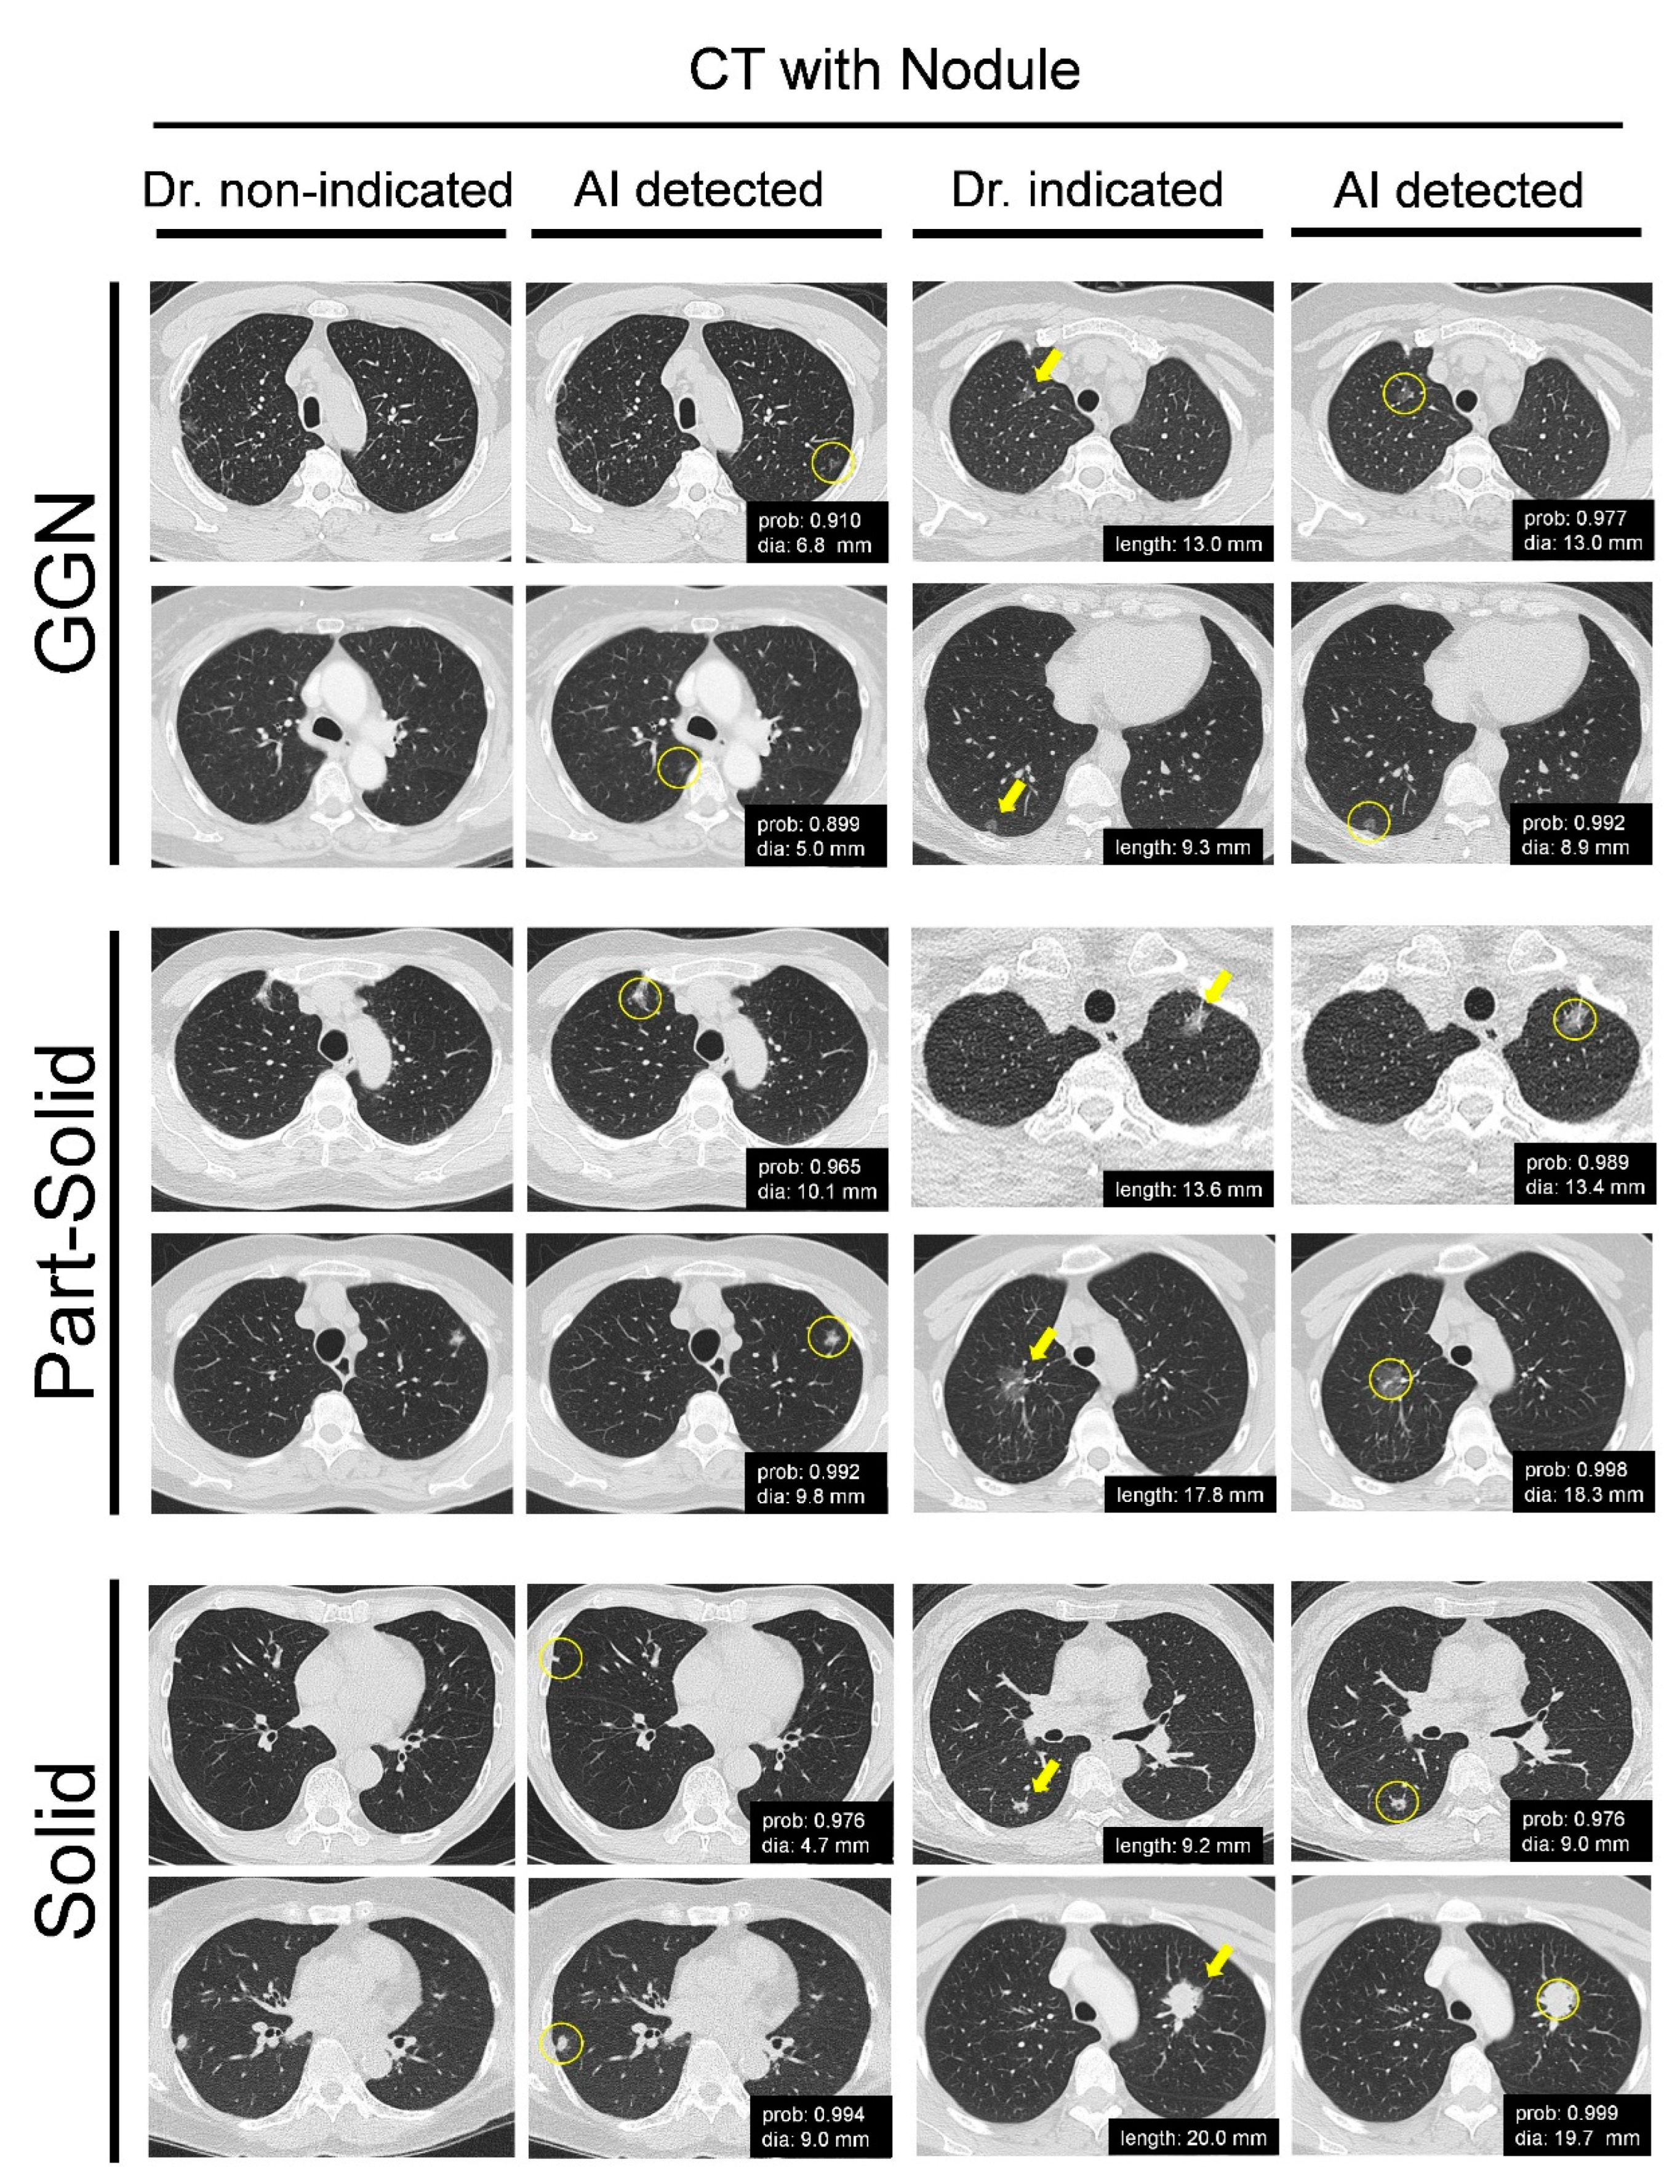

3.1. AI-Embedded CT Screening Marks the Varied Nodules in the Regular LDCT Images Efficiently